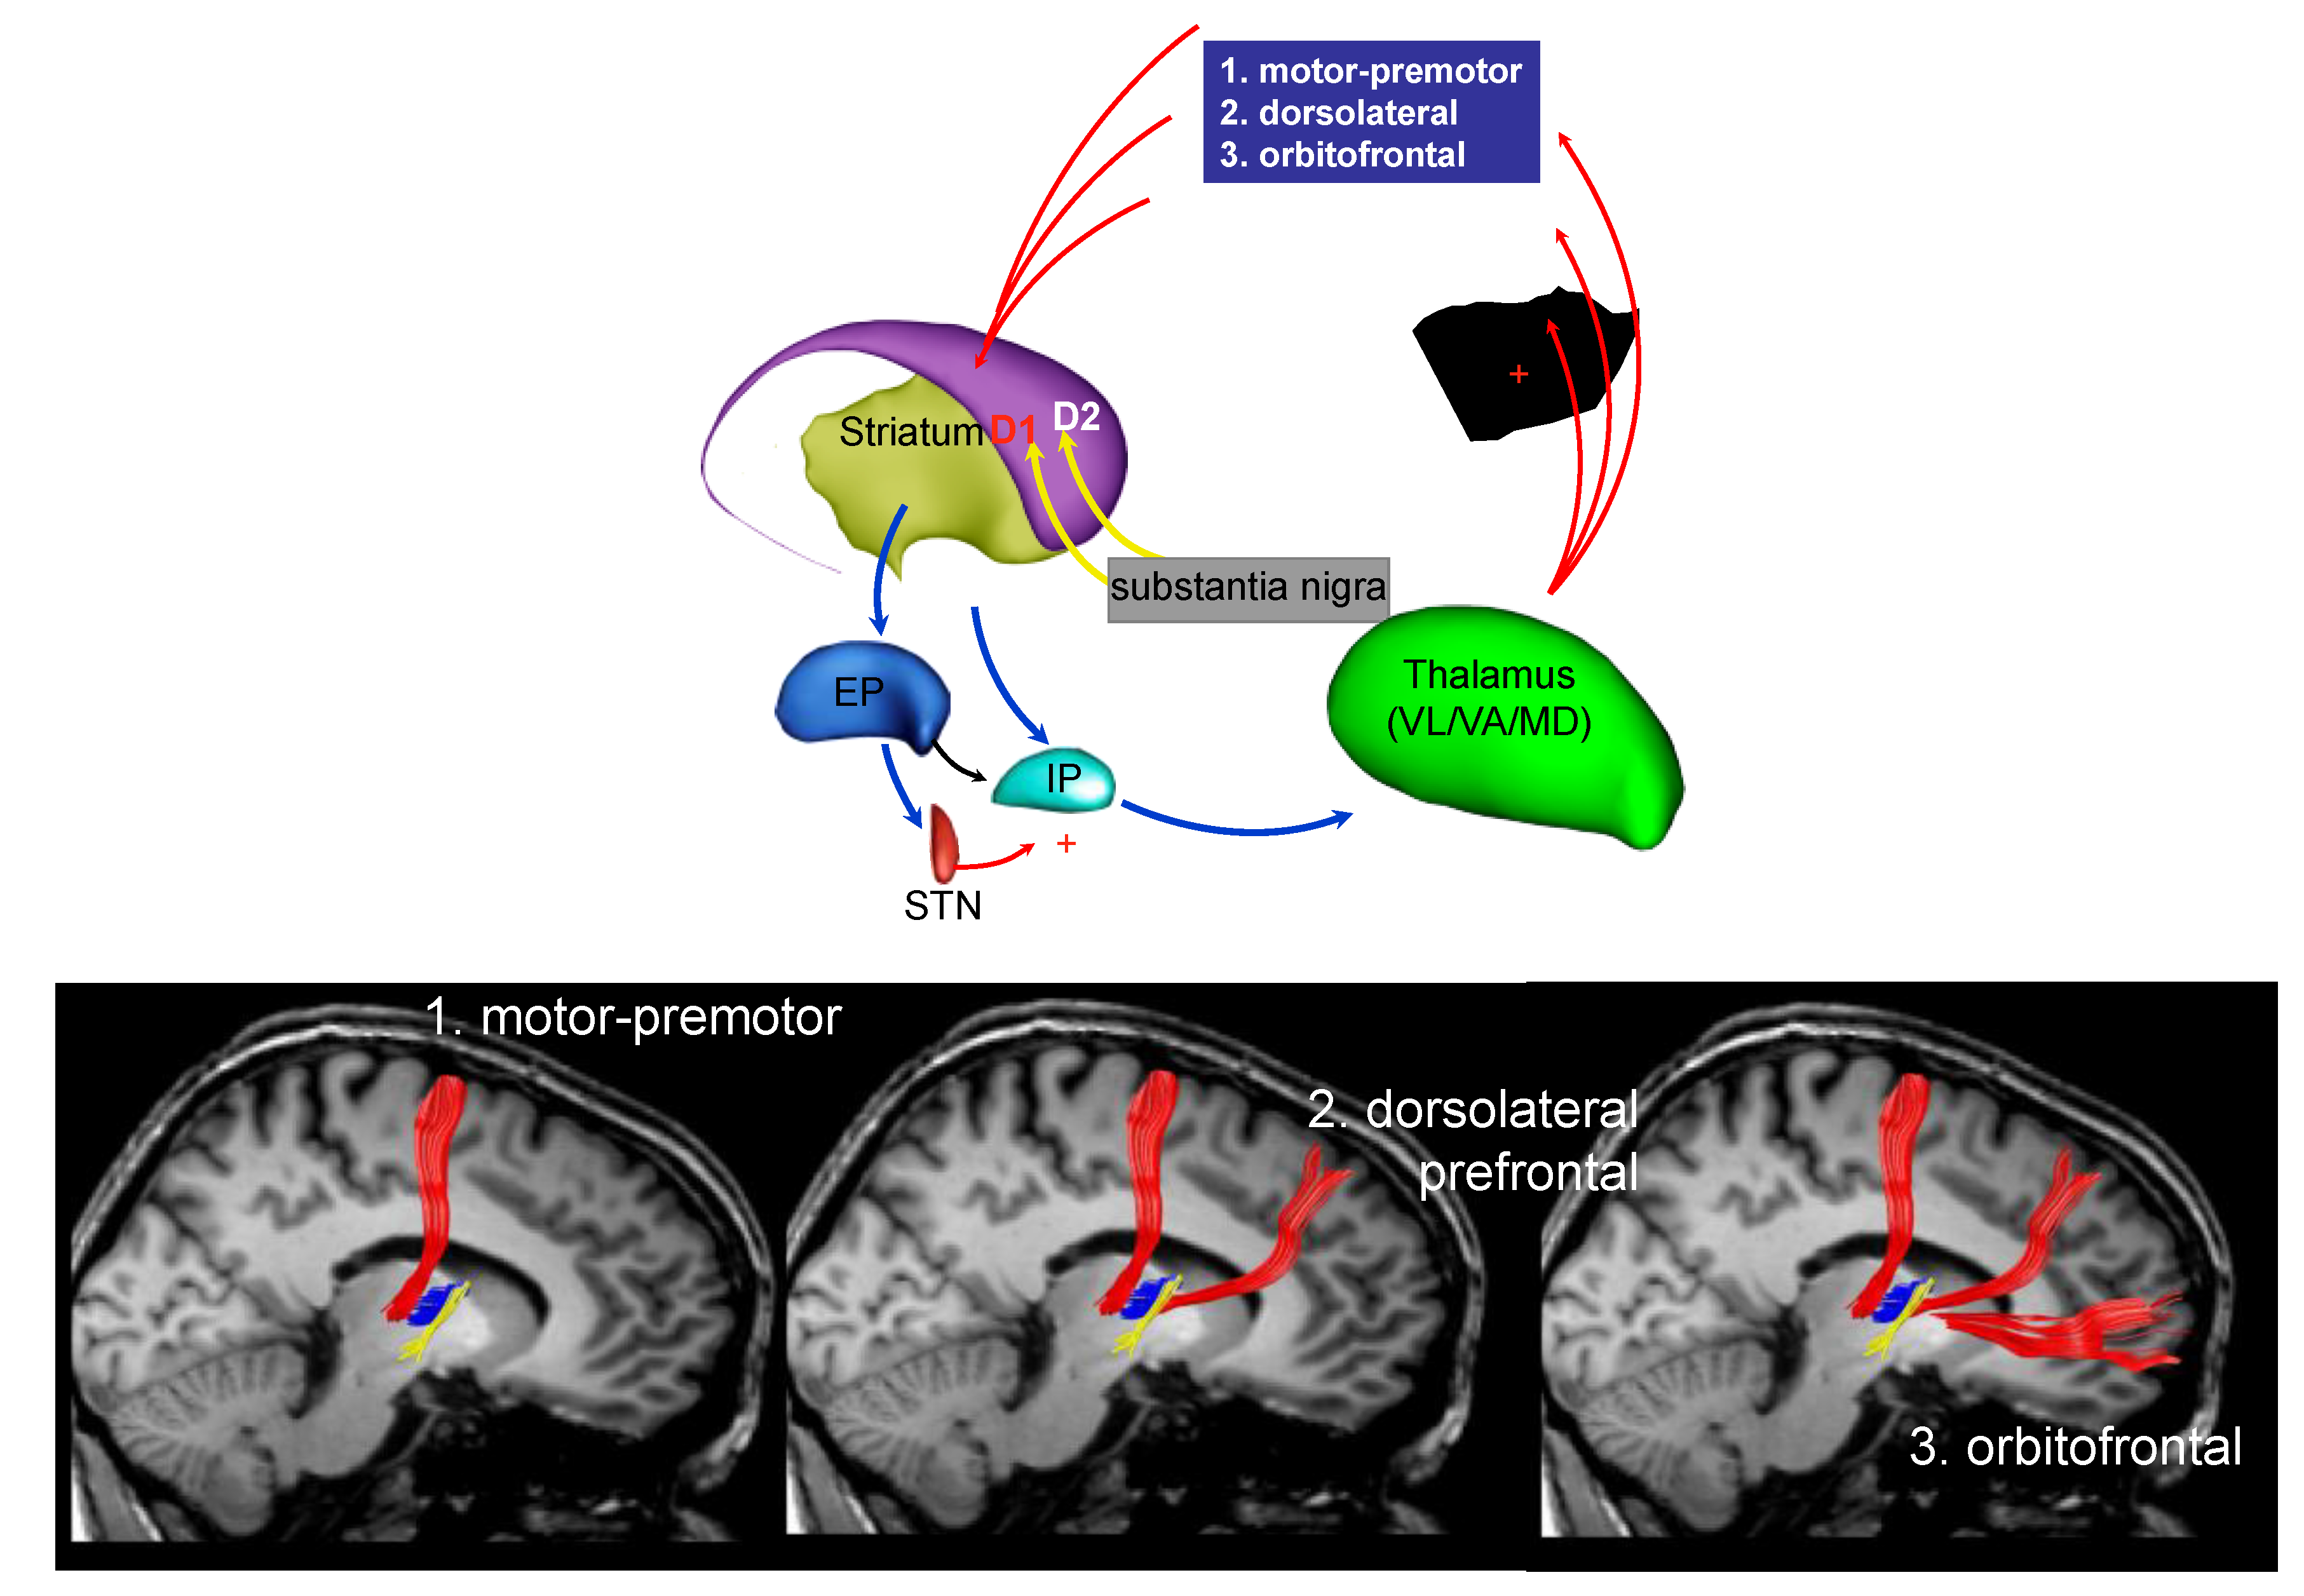

3. Parkinson’s Disease Subtypes Identified by Tractography